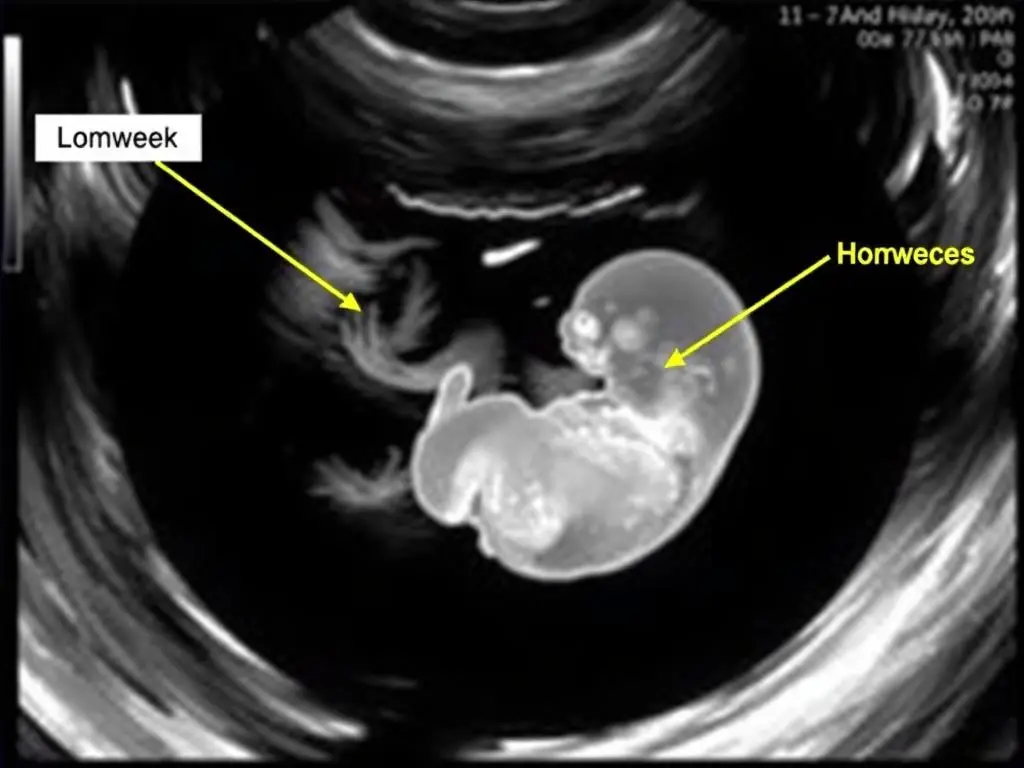

Zarodek w 8. tygodniu ciąży z widocznymi zawiązkami kończyn

W drugim miesiącu ciąży rozwój zarodka znacznie przyspiesza:

- Formuje się cewa nerwowa, z której powstanie mózg i rdzeń kręgowy

- Zaczyna bić serce (około 22-23 dnia od zapłodnienia)

- Pojawiają się zawiązki kończyn, oczu i uszu

- Rozwija się układ pokarmowy

- Pod koniec 8. tygodnia zarodek ma około 1,6 cm długości i waży około 1 g

- W tym okresie kobieta może odczuwać pierwsze objawy ciąży: nudności, zmęczenie, wrażliwość piersi [6]